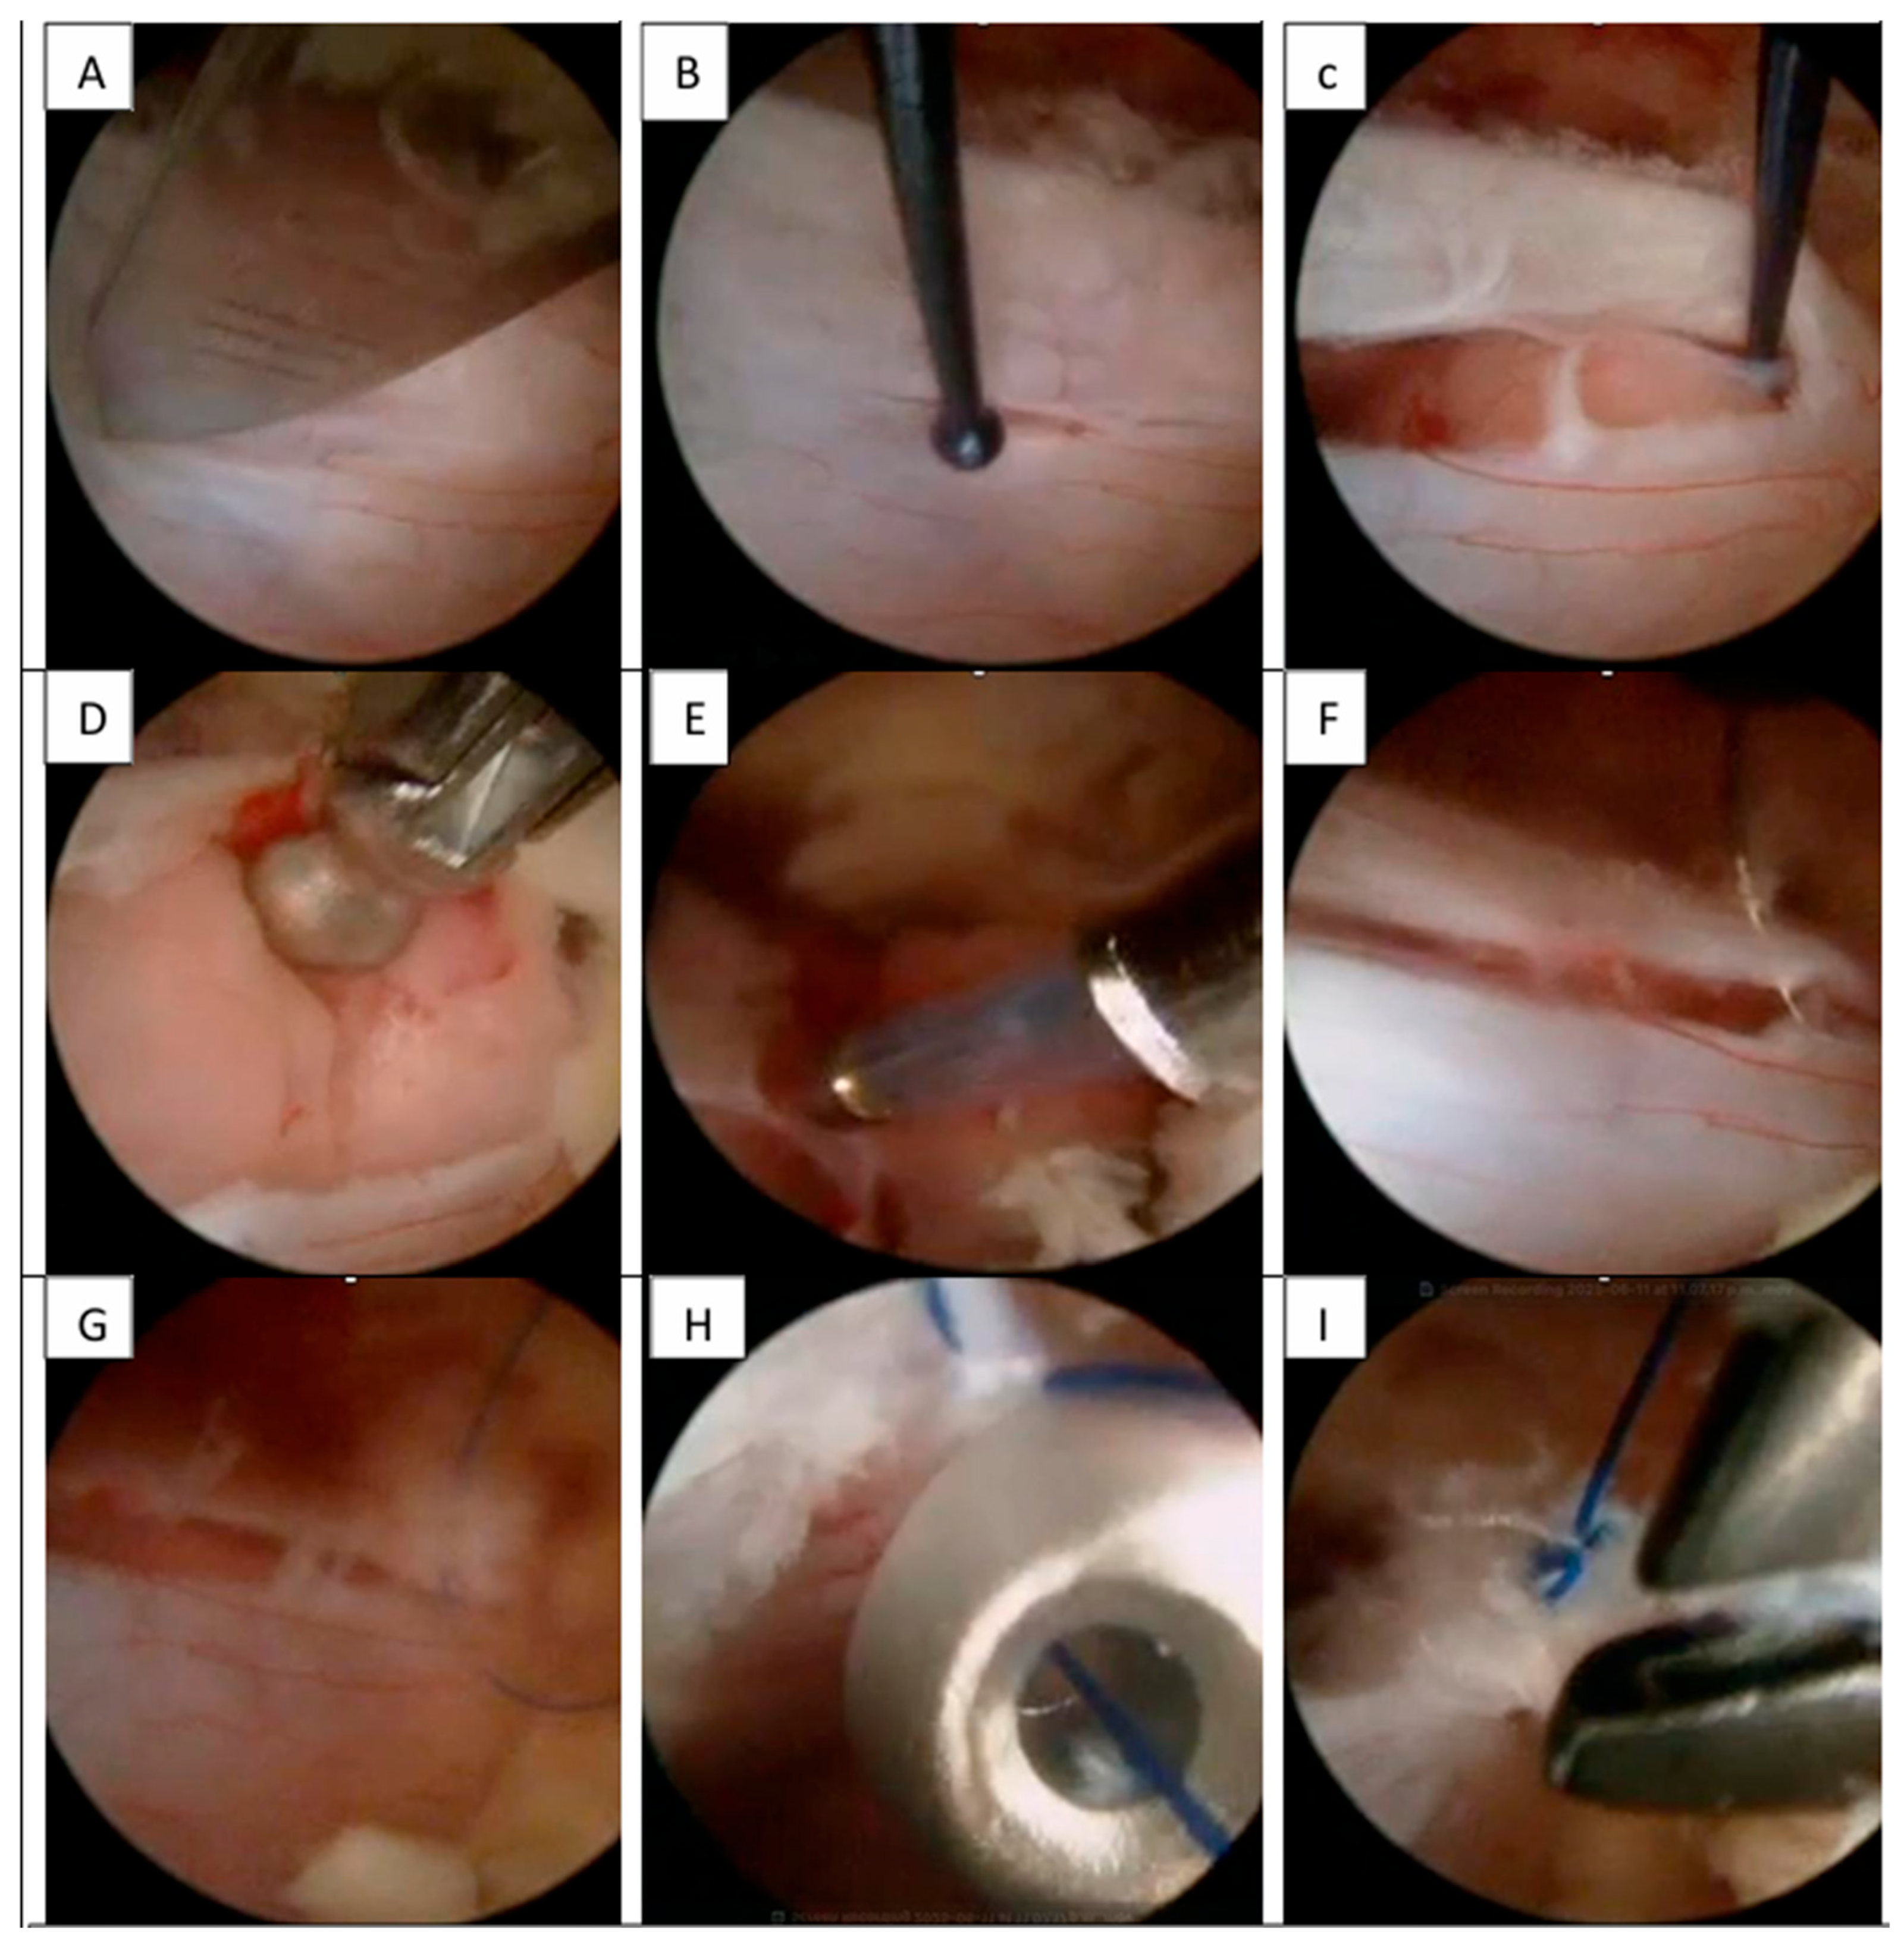

Step 1—The incision was marked as previously described. In all cases, the incision was performed with a #20 scalpel blade oriented at 90° to the fluoroscopic landmarks. We performed this same incision in the fascia and angled the scalpel in a cephalocaudal direction to open the muscular tissue and facilitated the creation of the working space for continuous water flow without increasing pressure in the surgical chamber [

9].

Step 2—The 30° biportal endoscope (or standard 30° arthroscope) and working instruments were introduced directly, without the use of serial dilators. This saved time and preserved tissue integrity by minimizing disruption during the creation of the working space.

Step 3—Continuous saline irrigation was maintained using gravity (70–100 cm height) or a pump system (20–30 mmHg) at room temperature. Minimal tissue dissection was performed with disc forceps. Subsequently, the working space was enlarged using plasma RF as necessary. A flavectomy was performed using an over-the-top technique, extending the laminotomy bilaterally to the cephalic and caudal lamina while preserving anatomical structures. We aimed to achieve a wider “O-cut” decompression as necessary and proceeded when all neural structures could be visualized free of ligamentum flavum [

10].

Step 4—With the exposure of the thecal sac, a vertical midline durotomy of 2.0 to 2.5 cm was performed, adjusted to the size of the lesion. We recommended a maximum 3 cm incision to facilitate manipulation of the dura for larger lesions (this step was critical for the chosen closure technique).

Step 5—Following dural opening, water flow was strictly controlled between 15 and 20 mmHg (pump) or by lowering saline bags to 50–60 cm (gravity). This achieved a constant minimal flow sufficient for dissection without displacing nerves from the dural sac margin. Tumor resection was performed using conventional microsurgical techniques, such as fragmentation or en-bloc Gross Total Resection (GTR). This was feasible in UBE because standard instruments such as Rhoton or Penfield dissectors, curettes, and pituitary forceps were utilized.

A distinct advantage of UBE was “intermittent hydrostatic dissection”. This involved temporarily increasing the pump flow from 15 mmHg to 30 mmHg to dissect adhesions. However, we recommend using this technique for a maximum of 1 min to avoid complications associated with high pressure, such as elevation of intra-cranial pressure. For hemostasis within the canal, only specific UBE plasma electrodes were used. The resection involved a combination of dissection and traction with Rhoton dissectors, nucleus pulposus forceps, and pituitary forceps to ensure safety. Once resection was complete, the hemostasis was strictly verified. With a 30° UBE endoscope, it was possible to obtain a panoramic “scanning effect” that improved all visual fields [

11,

12,

13].

Step 6—After resection, dural closure was a challenge. We performed a continuous simple suture with extracorporeal double knots. Hemoclips were another safe option for dural closure in short durotomies (<1 cm), with or without a synthetic dural patch. We reserved the synthetic patch primarily for cases of asymmetrical dural opening [

14].

Surgical intervention was performed using the UBE technique via a right-sided approach based on spinometric landmarks (

Figure 2), with minimal muscular tissue disruption. Bilateral laminotomy of the cephalic and caudal laminae was completed with a wider “O-cut” using the over-the-top technique, followed by flavectomy using Kerrison rongeurs and curettes. A midline durotomy was performed with a #11 scalpel blade, and the incision was extended with a Rhoton dissector. Following visualization of the tumor, dissection was performed with Rhoton and Penfield dissectors. Hydrostatic dissection was facilitated by temporarily increasing the pump flow, after which the lesion was extracted with pituitary forceps without complications. Dural closure was achieved with a 6-0 prolene suture using the previously described technique (

Figure 3).